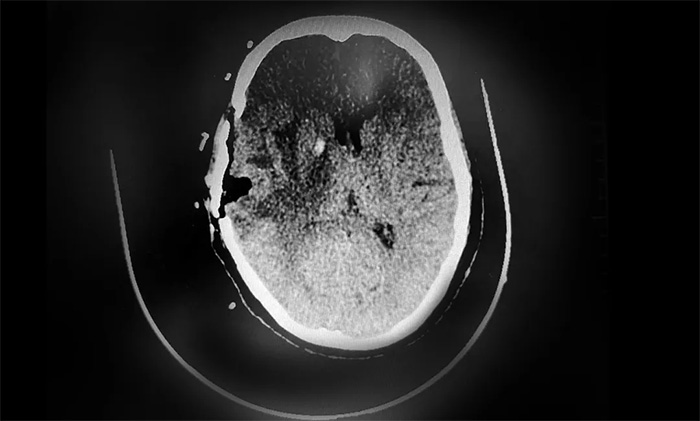

经过与患者家属充分沟通治疗方案并取得同意后,卢云鹤博士为患者开展了神经导航下颅内病灶切除术,在切除右侧颞叶肿瘤缓解占位压迫症状的同时,留取部分肿物送检,评估病理状态。

▲ CT复查示,肿瘤已被切除

根据初步病理检测报告,送检的样本为颞叶转移癌,结合病史及免疫组化,符合乳腺癌转移。后续,卢云鹤博士将根据分子病理检测结果,为患者制定实施包括靶向治疗等多学科联合的个体化综合治疗方案,改善患者生存状态,延长生存期。